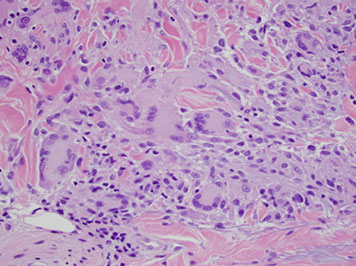

Histo: suprabasilar / intraepidermal blister and acantholysis

- "tombstones" - basal keratinocytes that remain attached to BM

IF: IgG and C3 deposition bwt cells in epidermis in fishnet or "chicken-wire" pattern

A) Pemphigus vulgaris, B) Pemphigus follicularis with suprabasal epidermal cleavage